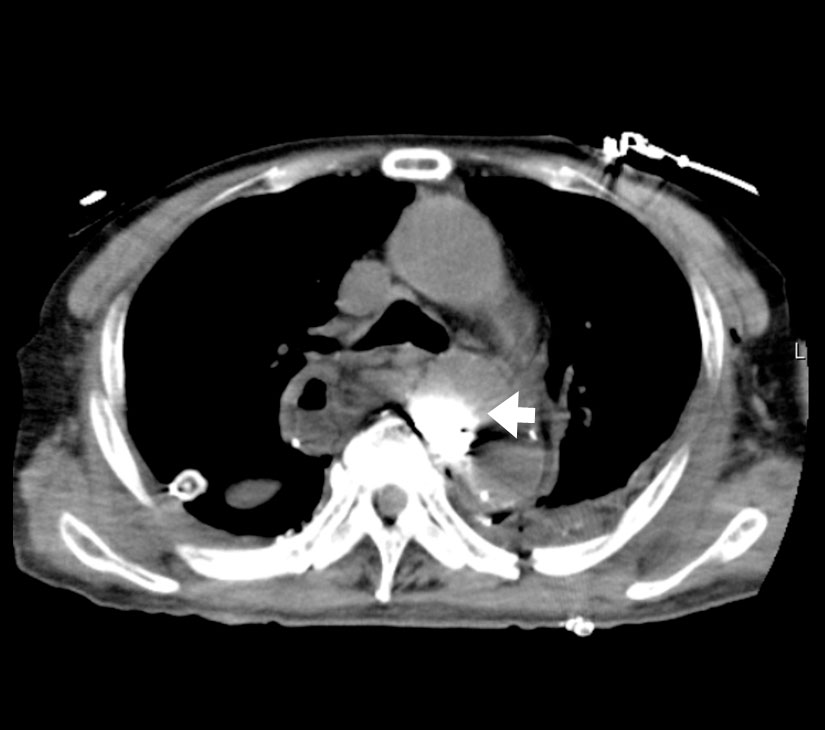

乳び胸、乳び腹水およびリンパ漏を含む、様々なリンパ液の漏出部を検出するために用いられるA Technical Review Korean J Radiol, 2014;15(6):724-732

- リンパ管造影における投与部位(例)